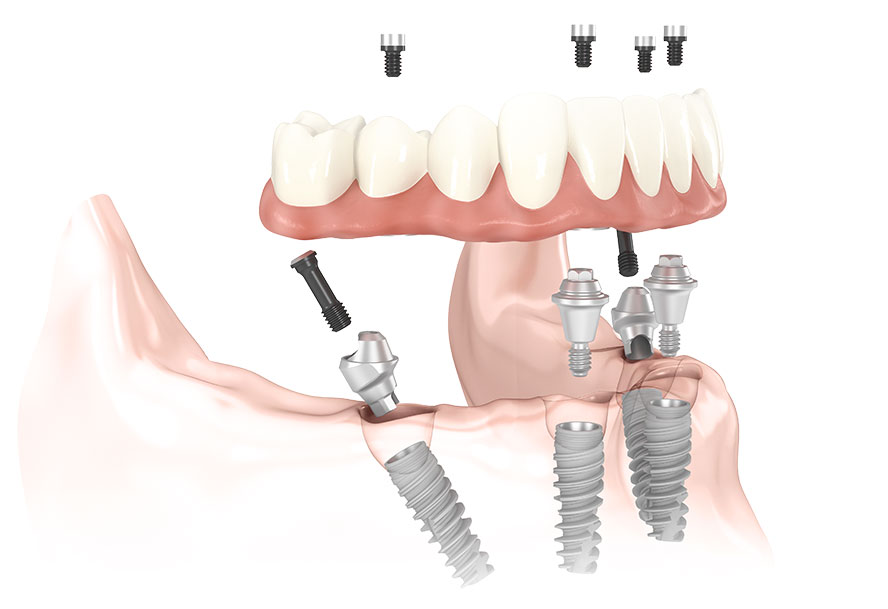

Full mouth dental implants is a revolutionary full-arch solution that offers stable, long-term tooth replacement. Four strategically placed implants support a fully functional, highly cosmetic set of teeth. With this advanced procedure, you never have to go without teeth! Temporary teeth let you enjoy your new smile the same day as implant surgery. Once your implants have fused with the bone, a permanent appliance is attached. Enjoy fast treatment, quick recovery and high satisfaction when choosing full mouth dental implants!